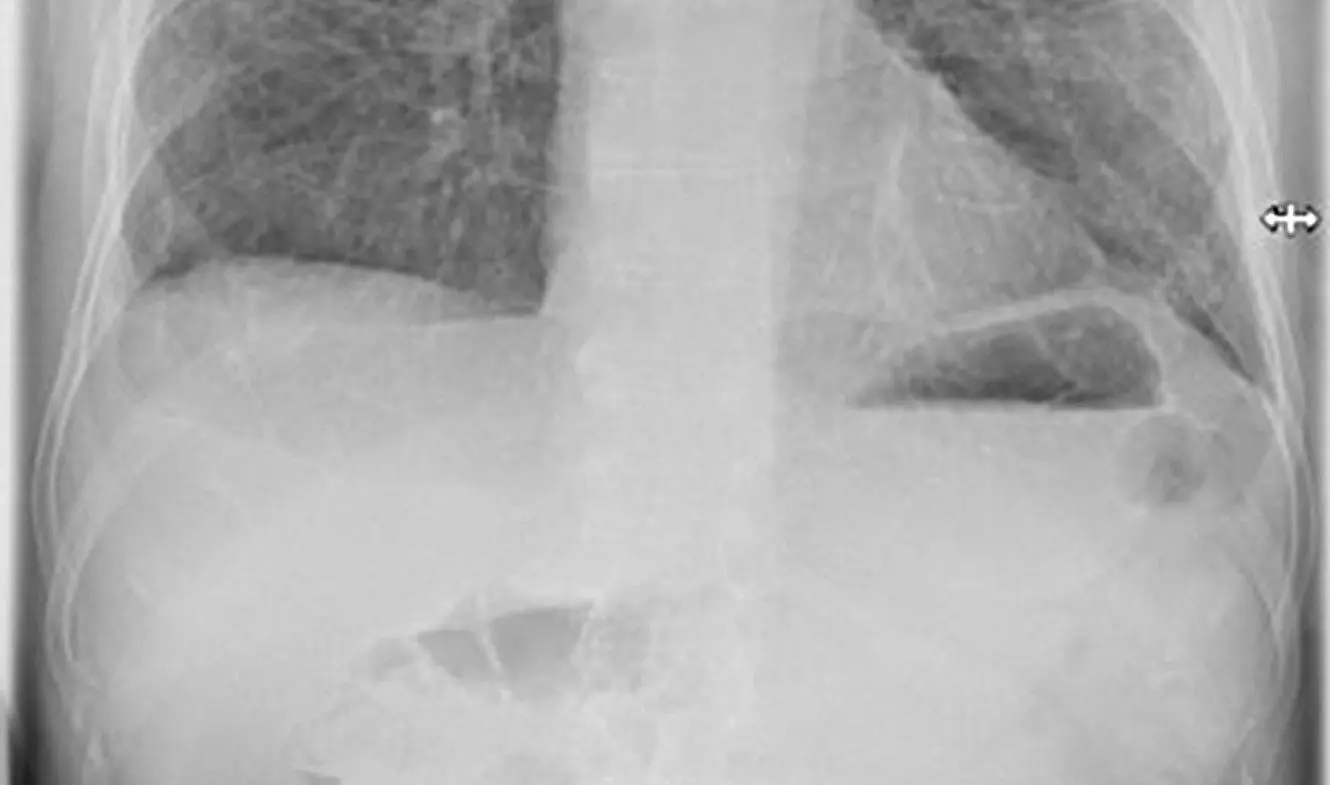

Gedächtnisverlust, Lungenschäden, Organversagen - die Liste möglicher Folgen einer Corona-Erkrankung ist lang. Sehr lang. Jetzt richtet sich Brandenburg mit speziellen Reha-Angeboten auf Post-Covid-Fälle ein. Es könnten Tausende werden.